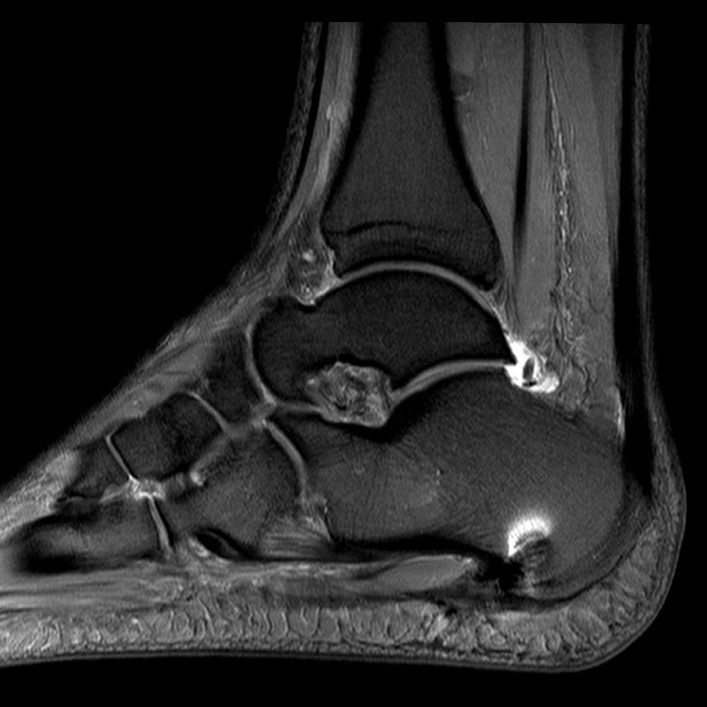

2.3. MRT

Eine Kernspinuntersuchung erlaubt eine Feindiagnostik des Tarsaltunnels, bei hoher Auflösung können Sehnen, Nerv, Arterie und Venen sowie Veränderungen der Plantarfaszie selbst oder des Faszienursprungs mit Signalalterationen dargestellt werden. Aufgrund der Sensitivität des Verfahrens kann unterschieden werden, ob es sich um eine Veränderung des Ursprungs der Plantarfaszie oder um eine weiter distal gelegene Problematik handelt. Gelegentlich findet man auch Teilrupturen etwas distal des Ansatzes (siehe Abb. 2). Diese Methode erlaubt auch eine Aussage über knöcherne Veränderungen.

Abb. 2: Teilruptur Plantaraponeurose in der MRT Diagnostik

Eine Teilruptur der Plantaraponeurose kann ursprungsnah oder auch einige cm distal des Ursprungs als Folge einer direkten Gewalteinwirkung auftreten.

Zum Lesen der Bildbeschreibung und zur Vollansicht bitte das Bild anklicken. Bild: Manfred Thomas

In seltenen Fällen findet sich eine komplette Ruptur der Plantaraponeurose als Ursache der Beschwerden (siehe Abb. 3).